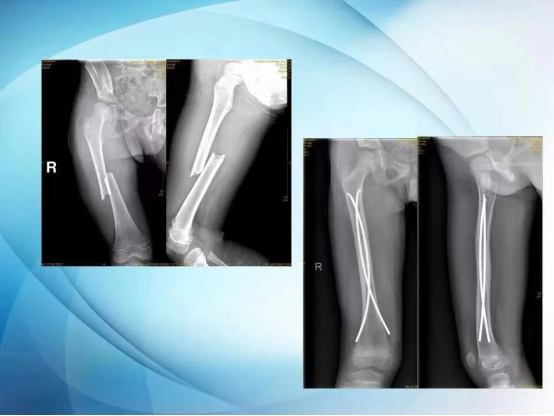

弹性髓内钉治疗儿童的长骨骨折,其特点是创伤小,进行微创操作不影响孩子的骨骼发育,对于骨折的愈合以及孩子以后的骨骼发育影响小。比较常见的骨折,比如胫骨骨折、股骨干骨折、尺桡骨骨折,对于这类长管状骨骨折,弹性髓内钉可以在骨折的一端进行微创操作:非常小的皮肤切口,一般在1厘米左右,通过c型臂透视下打入弹性髓内钉,弹性髓内钉在骨髓腔内走形,起到恢复骨折断端的力线、维持骨折断端的稳定而不伤及骨垢的作用。